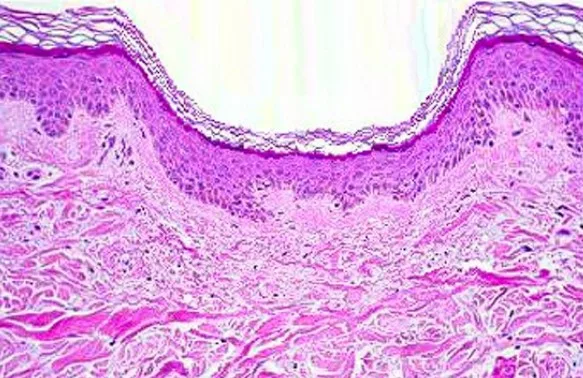

Schéma : Coupe histologique centrée sur la glande sébacée (ciblage Aviclear).

- 1726 nm : ciblage du sébum → action directe sur la glande sébacée.